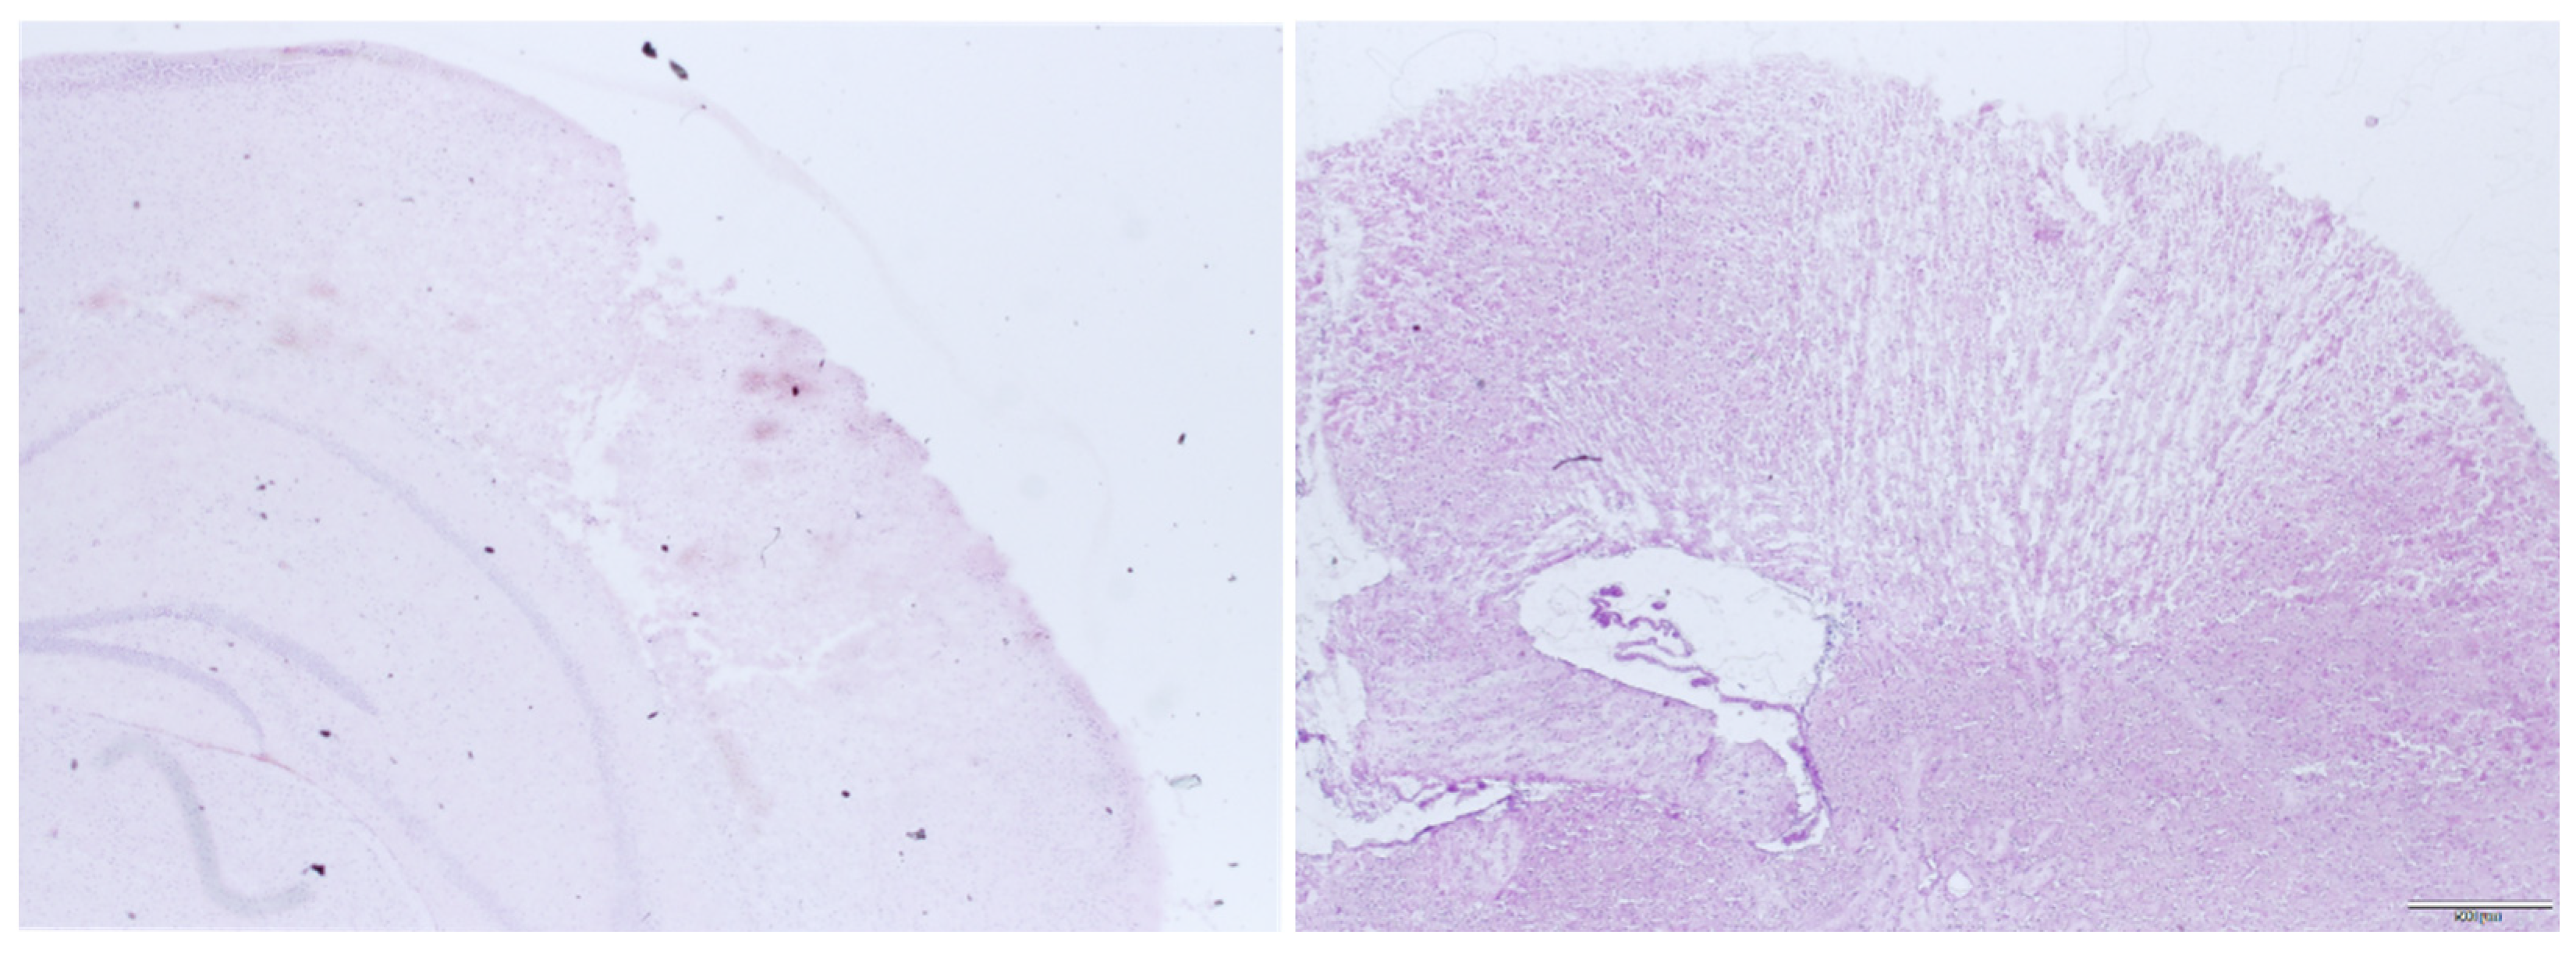

Figure 4 shows an example of the focal lesion 15 min after trauma and 24 h after trauma. It can be seen that there is a clearly demarcated area of contusion that is readily accessible to histologic volume measurement. In other damage models like weight drop, impact acceleration or fluid percussion, there is more diffuse subcortical damage, which cannot be evaluated by the examination used here [15,16,17,18,19].

Figure 4. Histological preparations of the right neocortex 15 min after CCI (left) and 24 h after CCI (right).